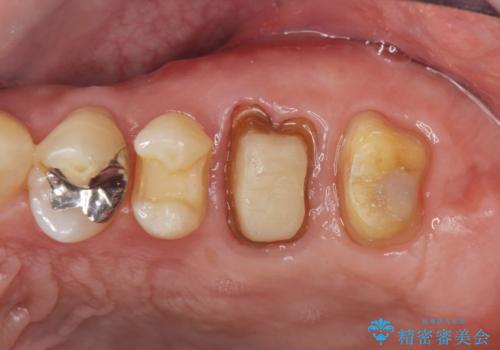

左下の欠損部には強度・表面性状に優れるストローマン社製インプラントを埋入し、合わせて噛み合う上顎の歯もクラウン再補綴による整備を行い安定した咬合関係の構築を目指します。

再補綴について

歯を失った期間が長くなると、対合する歯が伸びてくることによる補綴スペースの狭小化がしばしば見られます。

今回左下にインプラント治療を行うにあたり、対合する上顎の歯もいっしょに治療を行ったことで安定した咬合関係を構築することができました。